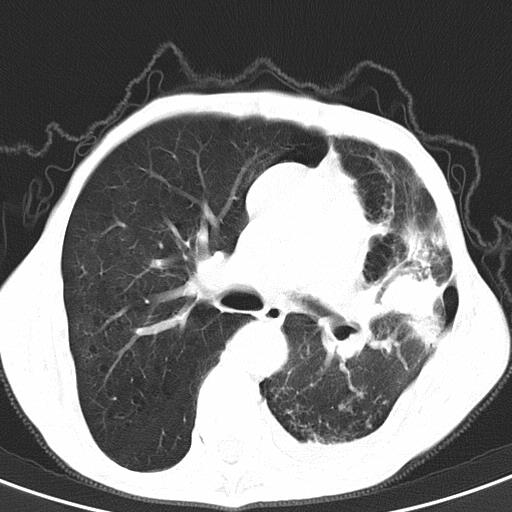

患者78岁,咳嗽胸闷一年余,近月来左侧胸痛;

建议强化,首先考虑左肺癌胸膜转移。

患者左侧胸廓塌陷说明是长期病变,考虑tb性胸膜炎可能性大,另外有明显的肺气肿,建议行结核菌素实验,或者增强扫描

1.慢支肺气肿。2.左肺感染,建议治疗后复查。3.左侧少量胸水。

1.慢支肺气肿。2.左肺感染,建议治疗后复查,待除外继发性肺结核合并感染。3.左侧少量胸水。

1)考虑左肺慢性感染性病变(结核可能)。2)左肺上叶周围型肺癌不排除;建议追踪复查。3)肺气肿。4)左侧胸腔积液,左侧胸膜增厚、粘连。